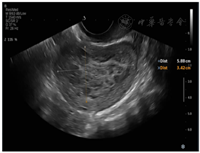

患者40岁,因"发现子宫肌瘤6年,明显增大伴月经量增多半年"于2020年2月21日入院。6年前患者体格检查发现子宫肌瘤,大小约2 cm,定期随访观察。近半年明显增大,出现月经量增多症状,复查超声提示子宫右壁查见大小约5.5 cm×4.7 cm×3.8 cm低回声。无腹痛、尿频、便秘、阴道不规则流血等症状,体质量无明显改变。患者14岁月经初潮,既往月经规律,孕5产1,人工流产4次,2005年因"阑尾炎"于外院行阑尾切除术。患者否认肿瘤家族史,无长期口服避孕药及其他激素类药物史。常规实验室检查、胸部CT及宫颈细胞学检查无异常。血清肿瘤标志物检测均未见明显异常。妇科检查:宫体后位,子宫如孕2个月大小,形态失常,质中,表面凹凸不平,无压痛。双附件区未扪及异常。盆腔超声检查:子宫右后壁肌壁间突向浆膜下查见5.9 cm×3.4 cm×5.0 cm的弱回声,边界清楚,提示子宫肌瘤可能;宫腔内查见大小约0.7 cm×0.5 cm×0.7 cm稍强回声,边界清楚(图1)。

注:右后壁肌壁间突向浆膜下查见5.9 cm×3.4 cm×5.0 cm的弱回声,边界清楚